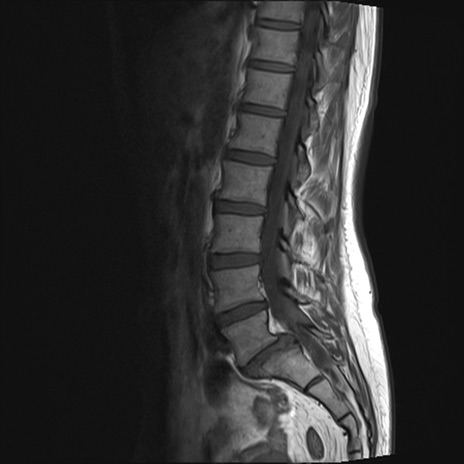

腰椎MRI

T2WI(矢状断像)